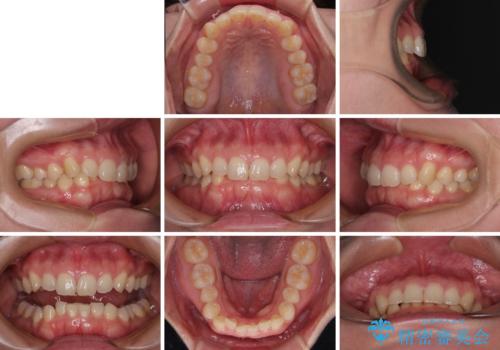

隠れた前歯が気になる ディープバイトのワイヤー矯正治療

- 下顎前歯が完全に隠れてしまっていることを気にして来院された患者様です。

下顎の臼歯が手前に傾斜していることで咬み合わせが深くなってしまい、下顎前歯が見えないほどに上顎前歯が覆い被さっている状態でした。

下顎臼歯を起き上がらせるためにユーティリティーアーチを使用し、一気に深い咬み合わせを改善することができました。